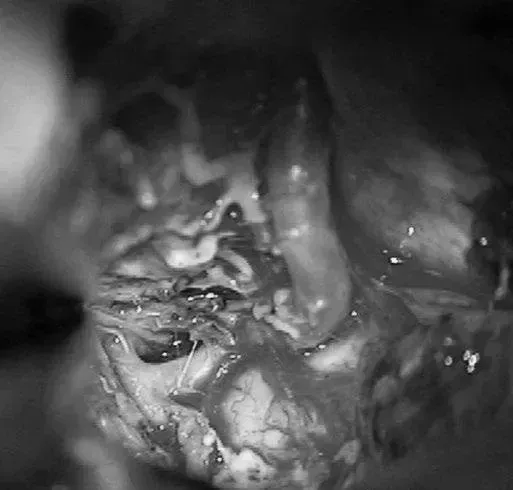

▼显露PCA周围至其ParOccA和CalcA(P2P)分叉

▼沿小脑幕见PCA的大脑脚段(P2A)和硬化的供血支。